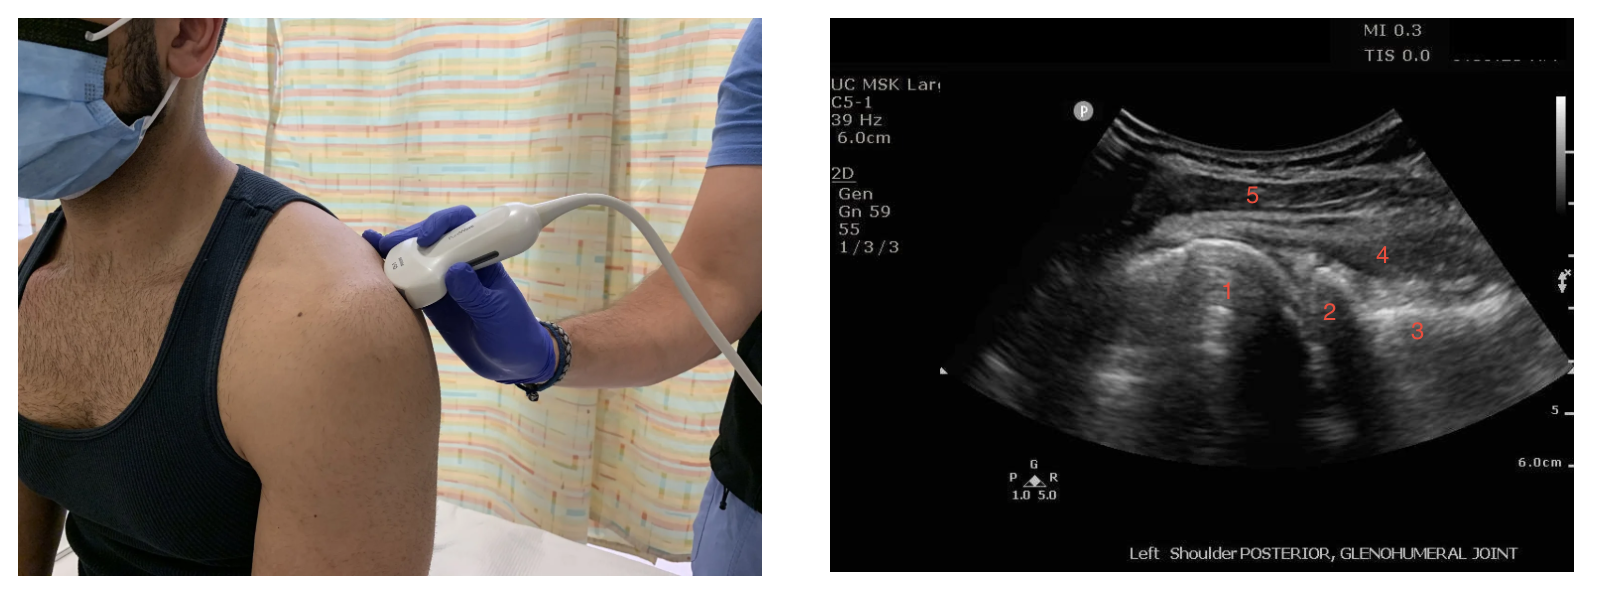

2) Ultrasound

While X-ray imaging will remain the primary imaging modality used for the diagnosis of shoulder dislocations, point-of-care ultrasound has been demonstrated to have essentially 100% sensitivity and specificity for the diagnosis of a shoulder dislocation when utilized and interpreted correctly (13,14). Furthermore, ultrasound can provide guidance for intra-articular anesthesia while also providing real-time feedback on success of reduction attempts without requiring repeat radiographs, though post-reduction radiograph should still be obtained as it is the current gold standard (14).

To acquire your image, stand behind the patient’s affected shoulder with arm adducted against their side and find the scapular spine then palpate laterally until you reach the glenohumeral space. Place a curvilinear or linear probe in transverse position parallel and slightly inferior to the scapular spine then slide lateral until you can visualize the glenoid and the humeral head (14). Probe marker should be oriented to the patient’s left. The location of the humeral head (circular structure immediately lateral to the glenoid) with respect to the glenoid can diagnose anterior versus posterior dislocations as the humeral head will be at a greater depth (farther from the probe) in anterior dislocations as opposed to more superficial (closer to the probe) in posterior dislocations (14,15). Following reduction, the humeral head should be in close approximation to the glenoid fossa and should be visualized to freely internally and externally rotate within the glenoid fossa (14,15). Normal shoulder anatomy is shown in images below. We recommend taking a look at this external site for a comprehensive video of normal anatomy vs anatomy seen under ultrasound guidance with shoulder dislocations.